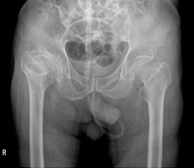

1. 분야별 전문 과장의 특성화 진료 좋은삼선병원 인공관절센터는 고관절, 무릎 관절, 어깨 관절, 수족부 관절 등 질환 부위별 특성화 진료를 통해 맞춤 치료를 시행합니다.

2. 인공관절시술 시행 병원(고관절 / 슬관절 / 견관절)좋은삼선병원 인공관절센터는 고관절, 슬관절, 견관절 등 다양한 인공관절시술을 시행하고 있습니다.

4. 저소득층 무릎 인공관절 후원 병원 좋은삼선병원 인공관절센터는 저소득 계층 독거 노인을 위한 무릎 인공관절 수술 지원 협약을 통해 부산시민 어르신들의 관절 건강을 책임지고 있습니다.